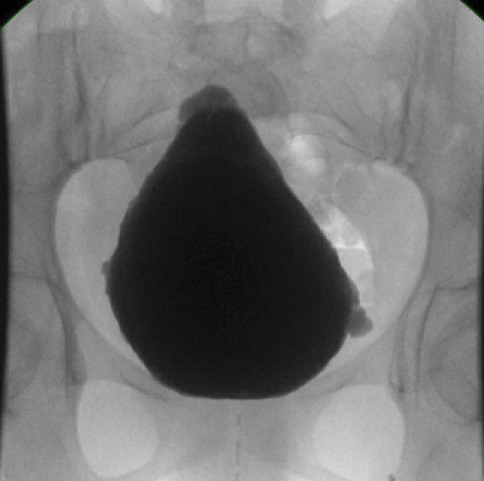

尿面综合征(UFS)是一种罕见的常染色体隐性遗传病,其特征为排尿功能障碍、微笑时面部表情倒置、LRIG2或HPSE2基因潜在突变。我们报告了两名被诊断为UFS的姐妹,她们使用骶骨神经调节(SNM)进行治疗。第一位患者,24岁,患有复发性尿路感染,慢性尿潴留和膀胱小梁,无膀胱输尿管反流(VUR)。基因检测鉴定出一种纯合子LRIG2变体。SNM治疗后,患者的排尿功能得到改善,置管次数减少。第二例患者,27岁,表现为5级左侧VUR,严重肾积水,左肾功能不全。尿动力学检查显示膀胱收缩。snm后,她的空后残留减少到30ml,允许独立排尿。两人脸上都露出了标志性的倒挂鬼脸。诊断影像和尿动力学证实神经源性膀胱,排除脊柱异常。治疗包括清洁间歇导尿(CIC)和SNM,增强膀胱排空,减少对导管的依赖。该病例强调了SNM作为UFS的一种有希望的治疗选择,可以提高排尿效率和生活质量。早期识别独特的面部表情对于防止上尿路损伤至关重要。泌尿科医生应该怀疑有排尿功能障碍和面部表情异常的患者存在UFS,并考虑将SNM作为可行的干预措施。有必要进一步研究SNM在UFS中的作用。

Urofacial syndrome (UFS) is a rare autosomal recessive disorder characterized by voiding dysfunction, inverted facial expressions when smiling, and potential mutations in LRIG2 or HPSE2 genes. We report two sisters diagnosed with UFS who were managed using sacral neuromodulation (SNM). The first, aged 24, had recurrent UTIs, chronic urinary retention, and a trabeculated bladder without vesicoureteral reflux (VUR). Genetic testing identified a homozygous LRIG2 variant. Following SNM, her voiding function improved, reducing the frequency of catheterization. The second patient, aged 27, presented with a Grade 5 left-sided VUR, severe hydronephrosis, and a nonfunctioning left kidney. Urodynamic studies revealed an acontractile bladder. Post-SNM, her postvoid residual decreased to 30 mL, allowing independent voiding. Both displayed the hallmark inverted facial grimace. Diagnostic imaging and urodynamics confirmed neurogenic bladder, excluding spinal anomalies. Management included clean intermittent catheterization (CIC) and SNM, which enhanced bladder emptying and reduced catheter dependence. This case highlights SNM as a promising therapeutic option in UFS, improving voiding efficiency and quality of life. Early recognition of the distinctive facial expression is critical to prevent upper tract damage. Urologists should suspect UFS in patients with voiding dysfunction and abnormal facial expressions, considering SNM as a viable intervention. Further studies on SNM's role in UFS are warranted.